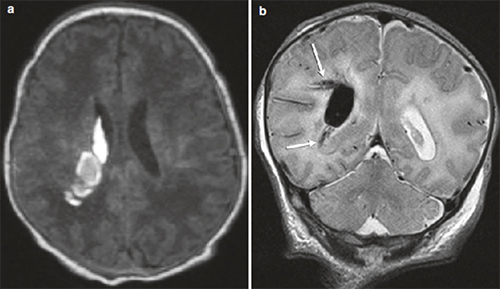

导致脑瘫的非进行性脑损伤病因,包括(1)发育不成熟的大脑(产前、产时或产后)、先天性发育缺陷(畸形、宫内感染) ;(2)获得性( 早产、低出生体重、窒息、缺氧缺血性脑病、核黄疸、外伤、感染);(3)脑瘫患儿出生时常常有早产或缺氧病史、以及感染、创伤等造成的脑损伤。常见的影像表现如下:

脑室出血造成脑组织梗塞